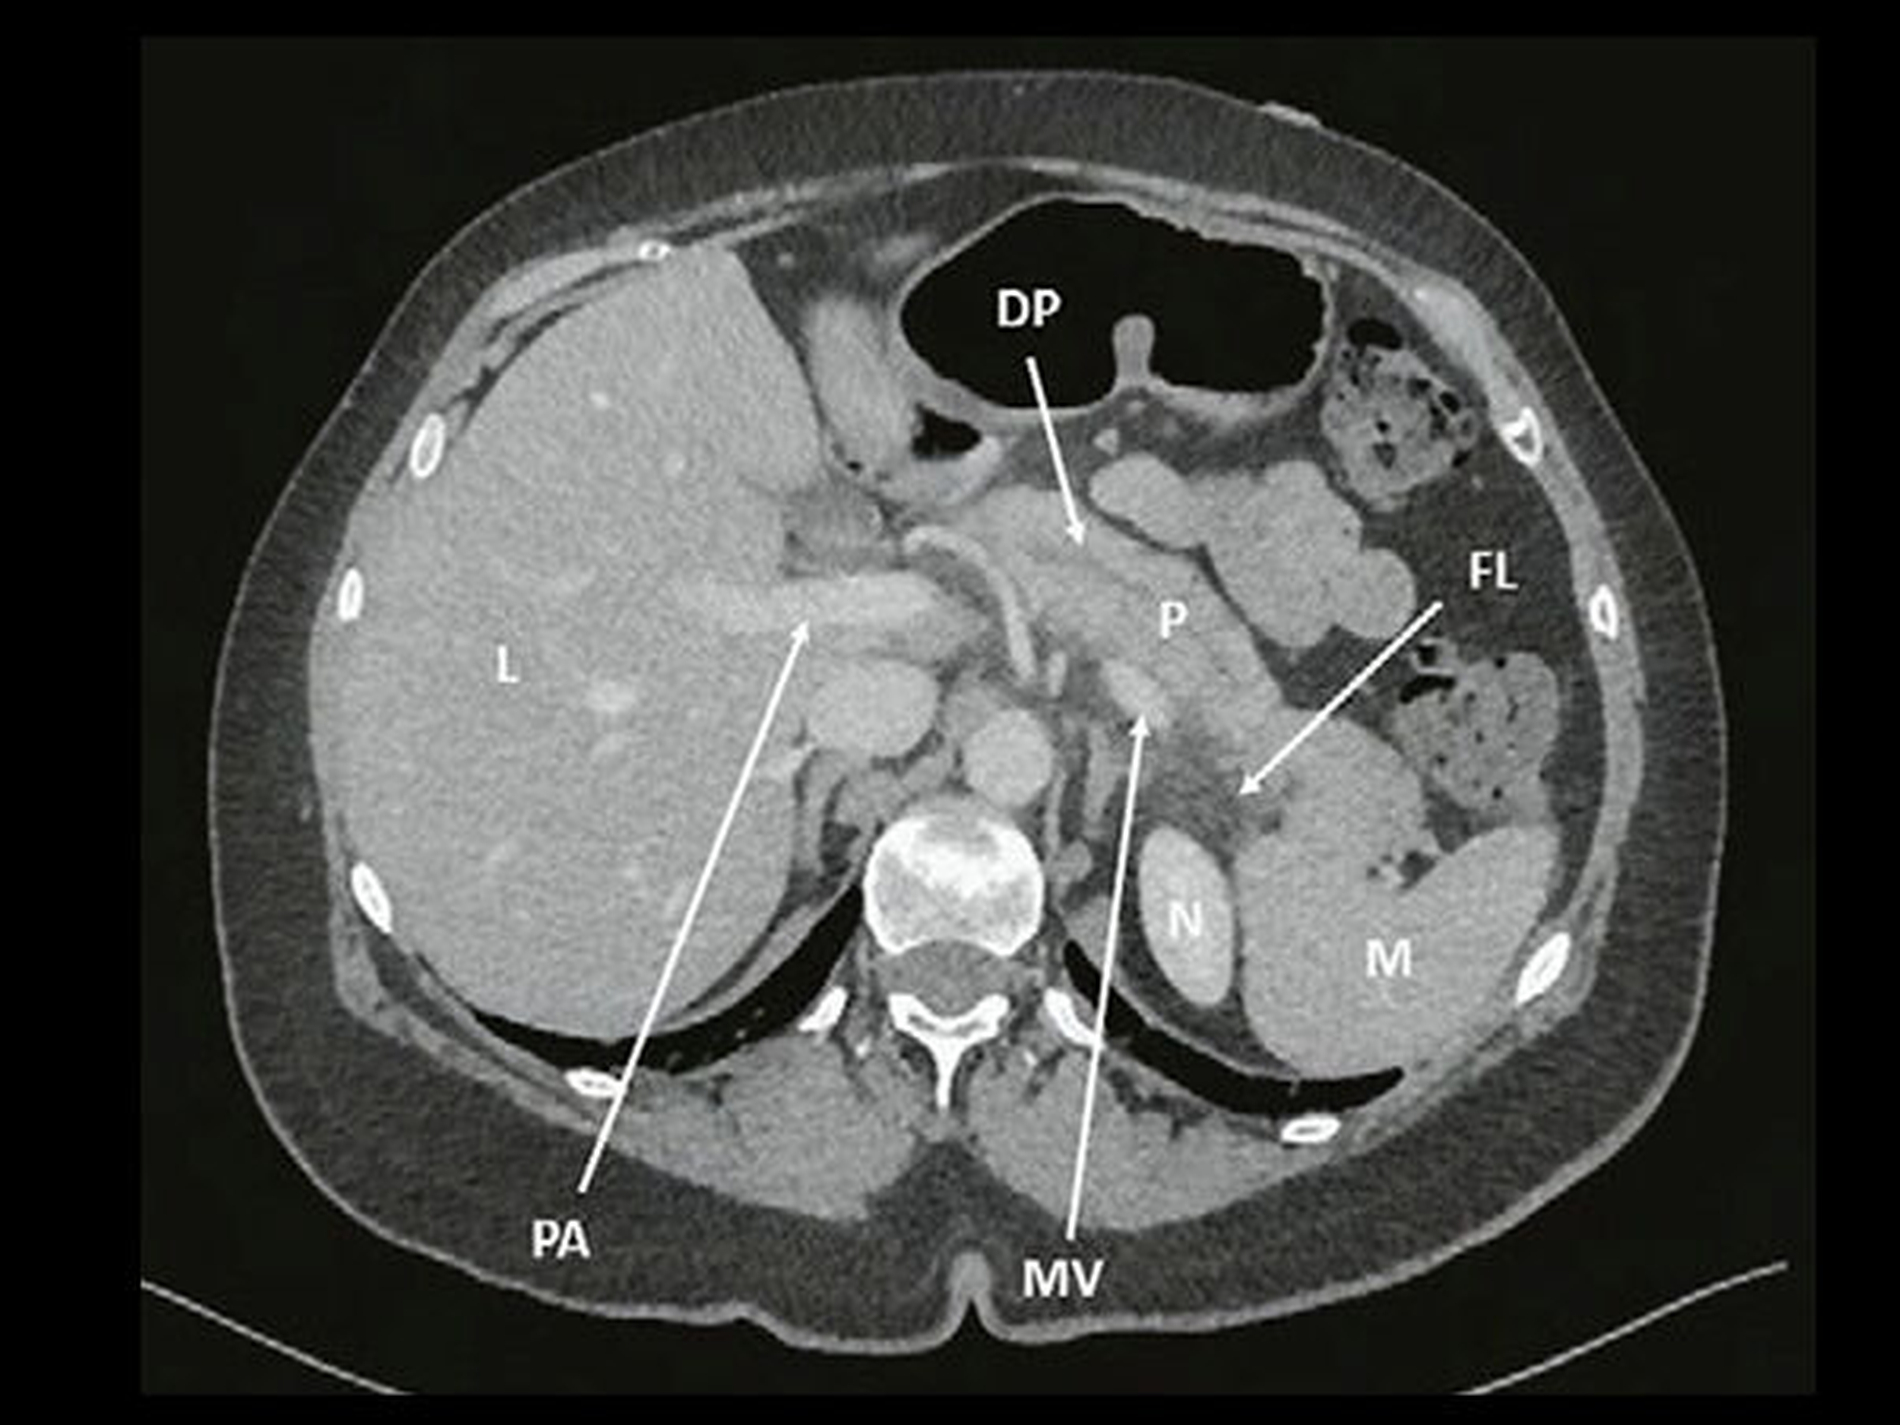

Zwei Tage nach Beenden der Antibiotikakombinationstherapie bemerkte die Patientin eine Appetitlosigkeit sowie ein Unwohlsein im Magen. Sie erwachte in der folgenden Nacht mit stärksten Oberbauchschmerzen und begab sich daraufhin frühmorgens in den medizinischen Notfalldienst. Die klinischen und laborchemischen Untersuchungen ergaben das Bild einer akuten Pankreatitis, deren Ätiologie vorerst unklar war. Anamnestisch konnten ein erhöhter Alkoholkonsum sowie fetthaltige Speisen als Auslöser ausgeschlossen werden. Sonografisch zeigten sich normale intra- und extrahepatische Gallenwege, womit eine (persistierende) obstruktive Ursache (Choleztzystolithiasis, Choledocholithiasis) ebenfalls ausgeschlossen werden konnte. Die ergänzend durchgeführte Computertomografie zeigte bekannte größenregrediente Zysten im Pankreasschwanz mit neu abgrenzbaren kleinfleckigen Verkalkungen der Zystenwände sowie wenig freie Flüssigkeit subsplenisch und peripankreatisch auf Höhe des Pankreasschwanzes (Abbildung 3).

Diese Befunde waren mit entzündlichen Veränderungen und somit mit der klinischen Präsentation und den Laborbefunden vereinbar. Aufgrund dieser Befunde wurde die Patientin auf der gastroenterologischen/viszeralchirurgischen Station des Inselspitals Bern zur weiteren Behandlung stationär aufgenommen. Unter Hydrierung, analgetischer Therapie sowie Nahrungskarenz stellte sich in der Folge eine Besserung ein und die Patientin konnte nach drei Tagen in gutem Allgemeinzustand nach Hause entlassen werden. Zahnmedizinisch zeigten die weiteren Recalls nach Initialtherapie erfreuliche parodontale Befunde, weshalb keine weiteren parodontalchirurgischen Therapien durchgeführt werden mussten (Abbildung 1 und 2).